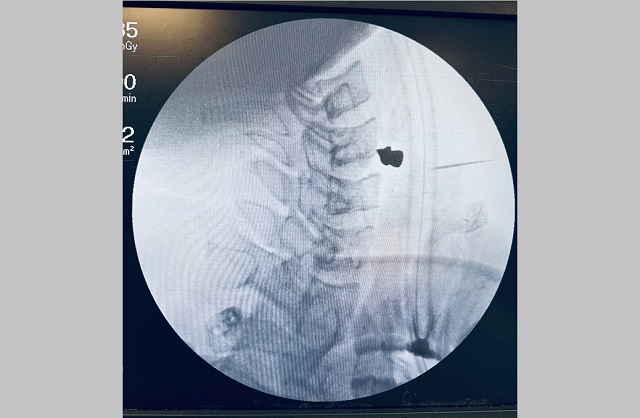

Мужчине было трудно глотать и говорить. КТ показало, что ни артерии, ни трахея, ни пищевод задеты не были — пуля каким-то чудом прошла через шею и остановилась в позвоночнике. Пациента тут же подняли в операционную.

Заведующий ЛОР-отделением Марат Гилялов вместе с заведующим отделением нейрохирургии №2 Георгием Майковым аккуратно извлекли пулю и зашили рану — вся операция заняла 20 минут. Сейчас пациент в палате — восстанавливается под наблюдением лечащего врача.

Фото: t.me/rkb_tatarstan